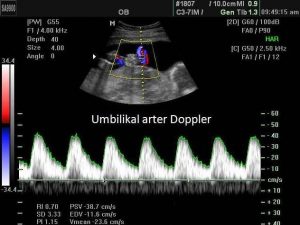

فحص دوبلر الشريان السري: في فحص دوبلر الشريان السري ، يتم فحص تدفق الدم من الطفل إلى المشيمة عبر الحبل السري. يساعد هذا الفحص على التأكد من حصول الطفل على كل ما يحتاجه من مشيمة الأم. إذا كانت الأم تحمل أكثر من طفل واحد أو كان معدل نمو الطفل منخفضا مقارنة بفترة الحمل ، يتم إجراء فحص دوبلر للشريان السري.

أثناء الحمل ، يمكن استخدام الموجات فوق الصوتية دوبلر لتقييم تدفق الدم إلى رحم الأم أو ، بشكل أكثر شيوعا ، تدفق الدم في الجنين. تدفق الدم في الشرايين له مظهر مختلف عن تدفق الدم في الأوردة. يكون التدفق الوريدي متجانسا إلى حد كبير ، دون تغييرات أثناء الدورة القلبية ، ما لم يقم الجنين بحركة تنفس أو كانت هناك حالة سريرية غير مواتية ، مثل تأخر النمو داخل الرحم. ومع ذلك ، فإن تدفق الدم الشرياني مختلف تماما. بغض النظر عن الشريان الذي يتم تقييمه ، فإن سرعة تحرك الدم عبر الشريان ستتغير خلال كل دورة قلبية. ستكون السرعة عند الحد الأقصى عندما يزيل القلب الدم في البداية من البطين الأيسر ، والذي يسمى الانقباض. ثم يبدأ البطين في الامتلاء مرة أخرى خلال الفترة التي تسمى الانبساط. أثناء الانبساط ، ينخفض معدل تدفق الدم في الجسم تدريجيا ، ليصل إلى أدنى مستوى له في نهاية دورة الملء ، والذي يسمى التدفق الانبساطي النهائي ، قبل العودة إلى السرعة القصوى مع انقباض القلب التالي. هذا التدفق ، الذي يحدث عندما ينقبض القلب ويطرد الدم ، هو ما يشعر به شخص ما عندما يفحص نبضنا.

في الموجات فوق الصوتية دوبلر ، يتم قياس انفجار تدفق الدم عندما ينقبض القلب ، ثم يطرد الدم ، على أنه تدفق (تدفق) الدم الانقباضي. الانبساط (د) ، الذي يشير إلى امتلاء القلب ، يقاس في النهاية ، قبل انقباض آخر مباشرة. سيكون لشكل الموجة الذي تم إنشاؤه عن طريق قياس معدل تدفق الدم نمط سن المنشار المميز على شاشة الموجات فوق الصوتية. تمثل ذروة الموجة الانقباض ، وتمثل أدنى نقطة تيار نهاية الانبساطي. اعتمادا على الظروف السريرية ، فمن الممكن أنه لا يوجد تيار في الشريان في نهاية الانبساط ، وهذا ما يسمى غياب نهاية الانبساطي الحالي (دساي). في دساي ، سيبدو شكل الموجة على شاشة الموجات فوق الصوتية مثل ملصقات سن المنشار ، ولكن ستكون هناك فجوة بين كل سن.

يجب أن يكون التدفق في الشرايين السرية في الاتجاه الأمامي في ظل الظروف العادية. في الحالات السريرية الشديدة ، مثل تأخر النمو الشديد داخل الرحم ، قد ينعكس تدفق الدم الشرياني في نهاية الانبساط. في حالة عدم وجود تيار متردد ، سيظهر شكل الموجة كما لو أن” الأسنان “تشير لأسفل بينما تشير” الأسنان “لأعلى ، بدلا من”الفجوات بين الأسنان”. تذكر “”الأسنان” هي مجرد أشخاص عاديين لأشكال الموجة. تقليديا ، تمثل الأشكال الموجية التي تشير إلى أسفل تدفق الدم الذي يتحرك مؤقتا عكس الاتجاه الذي يهدف إلى التحرك فيه. وهذا ما يسمى نهاية الانبساطي عكس الحالي (دستا).